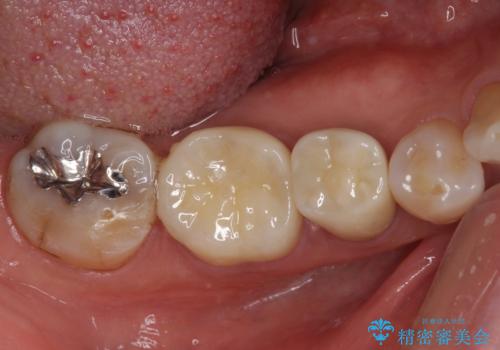

高強度のジルコニアクラウンとしたことで、強い咬合力でも壊れず、審美性を維持しやすい治療を行うことができました。